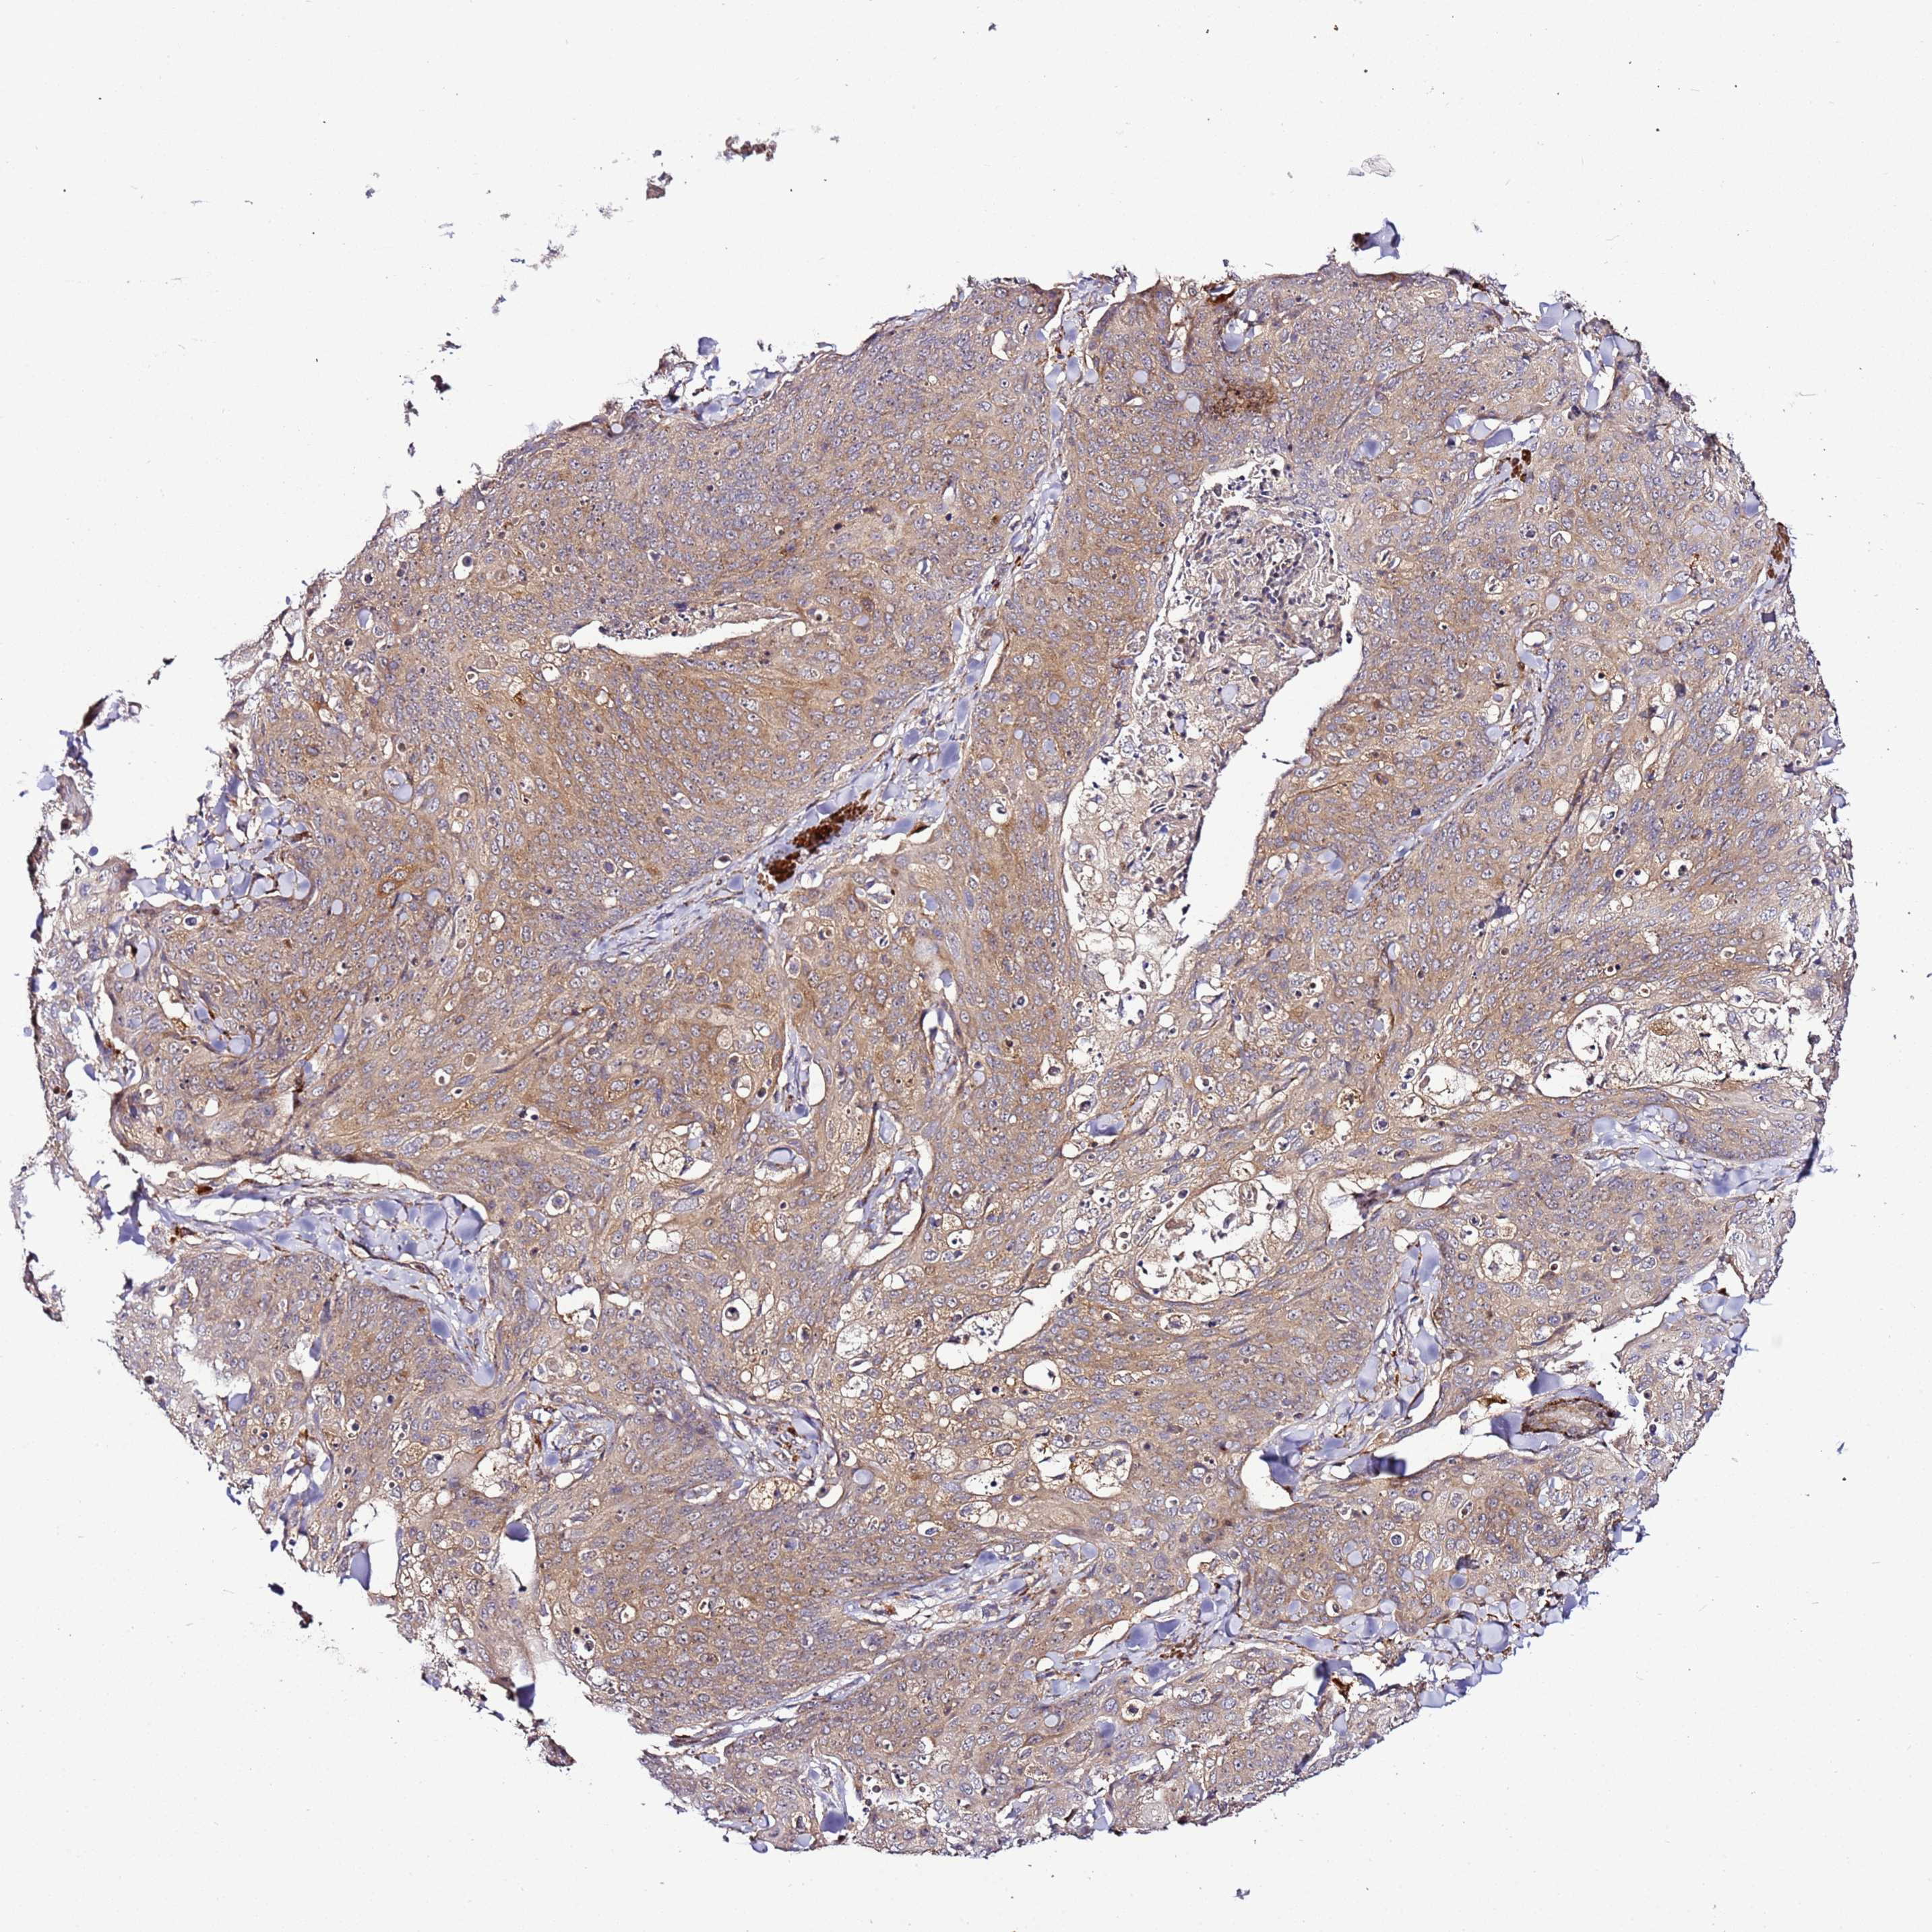

Basal cell and squamous cell cancer

SKIN CANCER - Protein expressioni

A mouse-over function shows sample information and annotation data. Click on an image to view it in a full screen mode. Samples can be filtered based on level of antibody staining by selecting one or several of the following categories: high, medium, low and not detected. The assay and annotation is described here.

Each image is clickable and will lead to virtual microscopy that enables deeper exploration of all samples and also displays staining intensity scores, fraction scores and subcellular localization as well as patient and tissue information for each sample.

Antibody HPA047497

Staining

High

Medium

Low

Not detected

Intensity

Strong

Moderate

Weak

Negative

Quantity

>75%

75%-25%

<25%

None

Location

Nuclear

Cytoplasmic/membranous

Cytoplasmic/membranous,nuclear

Basal cell carcinoma